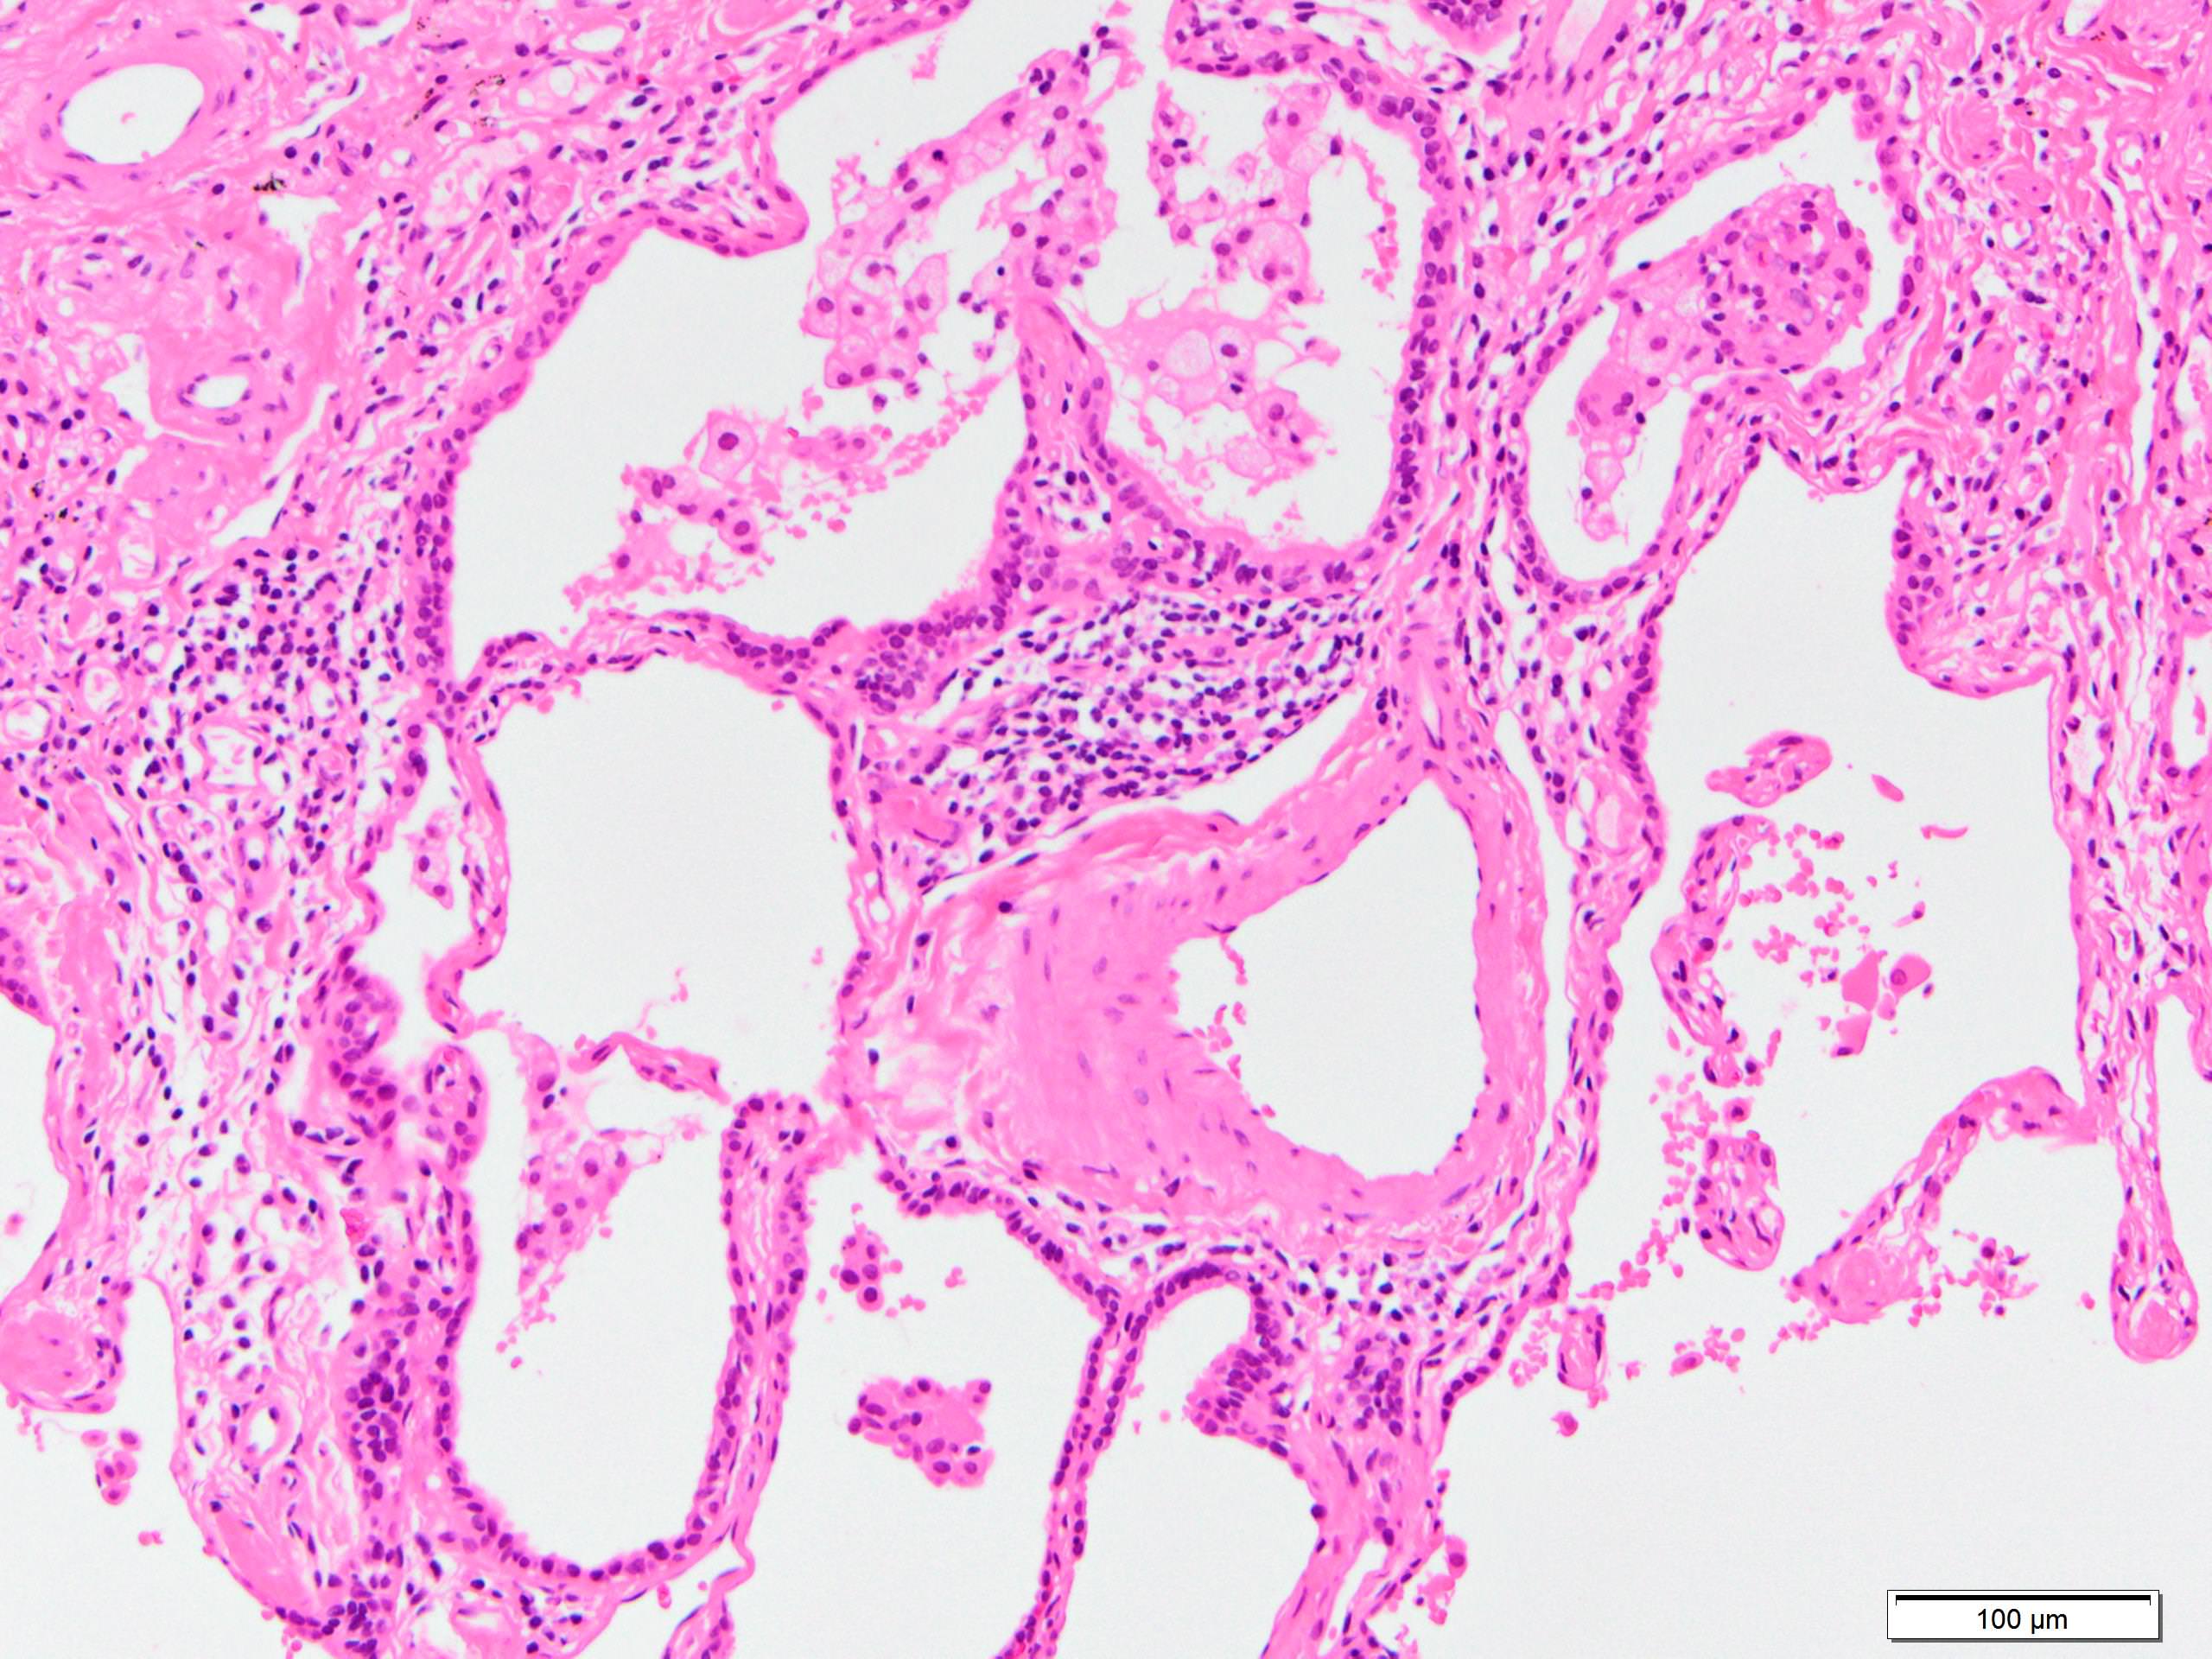

Microscopic (histologic) description

- Since there are few specific findings for NSIP pattern, it is essential to exclude other lung diseases on histology (Am J Respir Crit Care Med 2008;177:1338)

- Characteristic findings of NSIP pattern

- Diffuse and uniform inflammation ("temporal homogeneity") on low power of alveolar wall, bronchovascular bundles and pleura

- There are usually no normal alveolar walls in the affected lobules

- Cellular or fibrotic change

- Lymphocytic or plasmacytic infiltration

- Loose fibrosis

- Lung architecture is frequently preserved

- "Cellular NSIP" or "fibrotic NSIP" can be stated specifically in pathologist report

- Diffuse and uniform inflammation ("temporal homogeneity") on low power of alveolar wall, bronchovascular bundles and pleura

- It is quite rare to see pure NSIP on histology - typically there are focal findings of other interstitial lung disease (Histopathology 2014;65:549)

- Pertinent negative findings (Am J Respir Crit Care Med 2008;177:1338)

Microscopic (histologic) images

Contributed by Akira Yoshikawa, M.D.

Contributed by Akira Yoshikawa, M.D.

Positive stains

- Elastica van Gieson staining highlights the relative preservation of lung architecture